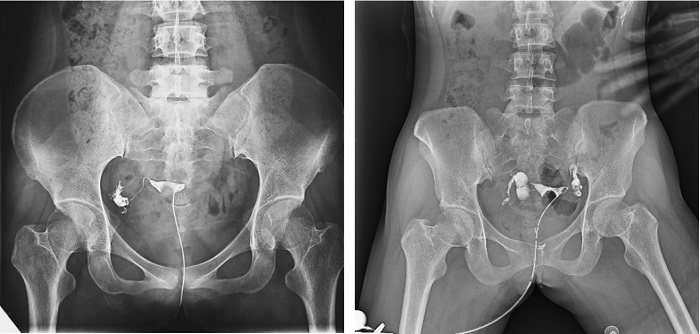

子宮輸卵管造影檢查損傷小,準確率高,是婦科檢查的常用方法。利用動態(tài)DRF進行子宮輸卵管造影檢查,大大超越了過去的檢查技術(shù),更加精準高效。動態(tài)DRF矩形采集面積大,一次曝光即可顯示整個盆腔,大幅減少觀察時間,可控的瞬時照射避免受檢者吸收過多X線,對育齡期女性檢查尤為重要??稍谠煊皠┝鲃拥倪^程中完成拍片,抓拍到關(guān)鍵圖像,幫助醫(yī)生更加清楚地了解到管腔的具體通暢情況及堵塞部位,提高診斷的精準性。

▲輸卵管造影

普利德動態(tài)平板DRF床體智能化程度更高,在進行子宮輸卵管造影檢查時,醫(yī)生可以通過調(diào)整床體起倒角度精準控制造影劑的流動方向和速度,并根據(jù)造影劑在輸卵管及盆腔里的顯影準確判斷輸卵管堵塞部位、程度及性質(zhì),極大提高了拍片效率和診斷的精準性。